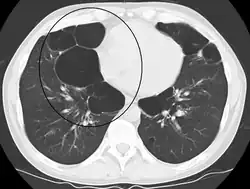

Bullous emphysema is a condition seen in patients with chronic obstructive pulmonary disease (COPD). The units making up the substructure of the lung (alveoli) become permanently enlarged due to the destruction of their walls. This leads to hyperinflation of the alveoli and, thus, the lungs. When this occurs asymmetrically, one lung can be larger than the other.[23] A severe variant of this condition is called giant bullous emphysema. On chest x-ray, one lung will be significantly more inflated than the other, causing a mediastinal shift. Bullous emphysema's radiographic appearance on x-ray mimics a tension pneumothorax. This presents a medical challenge as these diseases are treated differently despite appearing similarly on x-ray.[24][25]